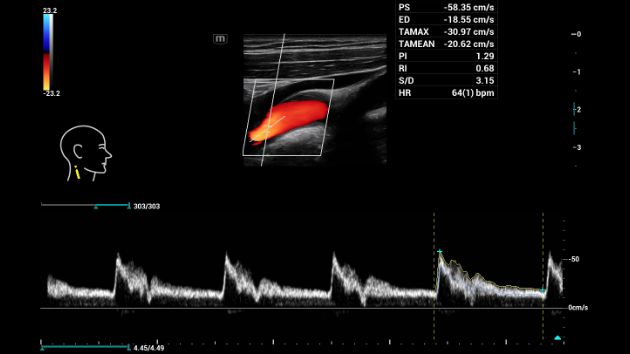

Consona presenta soluzioni nuove e concrete, che aiutano a effettuare diagnosi efficaci con semplicitĂ , rivolgendosi a un'ampia platea di pazienti. La serie mette a disposizione strumenti estremamente avanzati per rimanere all'avanguardia nella diagnosi cardiovascolare.

Galleria di immagini